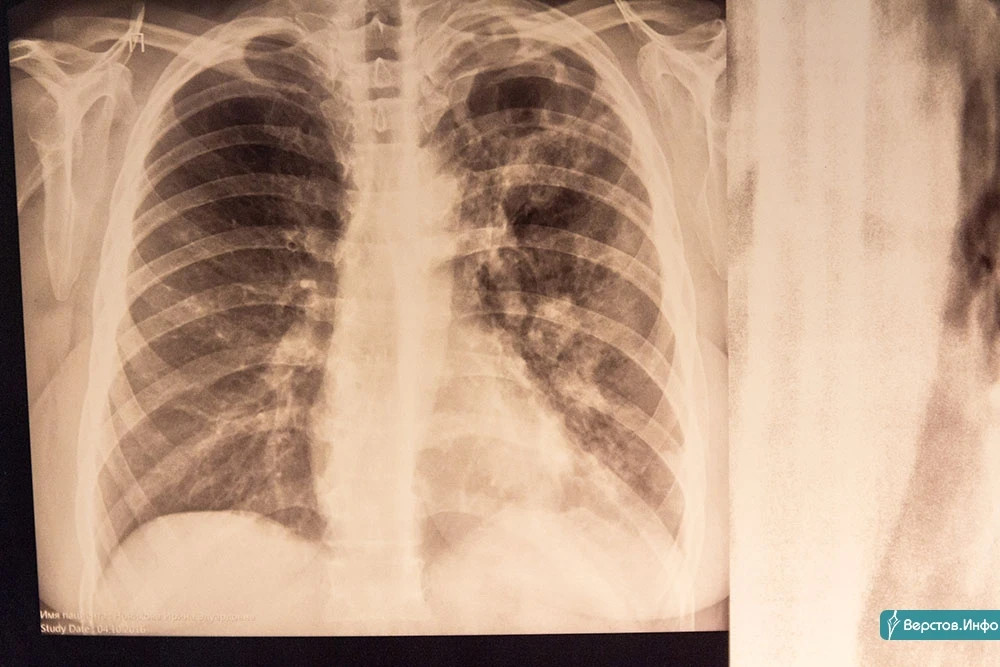

В Магнитогорске туберкулёз всё чаще сочетается с ВИЧ и всё более устойчив к лекарствам

Ежегодно 24 марта отмечают Всемирный день борьбы с туберкулёзом. Каждый год во всём мире этим коварным и опасным заболеванием поражается около 10 млн человек, 1 млн жителей Земли ежегодно погибают от туберкулёза.

Эпидемиологическая ситуация по туберкулёзу в России остаётся стабильно напряжённой. Наиболее неблагополучными территориями являются регионы, относящиеся к Дальневосточному, Сибирскому и Уральскому федеральным округам.

В Магнитогорске эпидемиологическая ситуация улучшается, но имеет свою специфику. Высокая заболеваемость туберкулёзом обусловлена значительным числом больных наркоманией в сочетании с ВИЧ-инфекцией. В 2023 году туберкулёзом заболели 167 магнитогорцев, в том числе восемь несовершеннолетних.

«Среди вновь выявленных случаев заболевания в 42 % случаев туберкулёз сочетался с ВИЧ-инфекцией. С каждым годом эта цифра неуклонно растёт. Наряду с этим отмечается ежегодное нарастание числа случаев туберкулёза с множественной лекарственной устойчивостью (МЛУ). В 2023 году каждый третий бацилловыделитель имел туберкулёзную палочку, устойчивую к обычным противотуберкулёзным препаратам. Причинами этого являются бесконтрольное применение населением антибиотиков и низкая санитарная культура горожан», – рассказывает главный врач ГБУЗ «Областная туберкулёзная больница № 3» Анатолий Шалагин.

По его словам, ВИЧ-туберкулёз и МЛУ-туберкулёз являются основными причинами высокой смертности населения от туберкулёза. Дело в том, что эти формы заболевания отличаются особой агрессивностью и трудно поддаются лечению. В 2023 году в Магнитогорске от туберкулёза скончались 15 человек.

Наряду с вакцинопрофилактикой важное место занимает своевременность прохождения населением профилактических медицинских осмотров на туберкулёз. Главная цель таких исследований – раннее выявление патологии. Чем раньше будет выявлено заболевание, тем быстрее оно будет вылечено полностью. Согласно действующим нормативно-правовым актам, все жители города должны ежегодно проходить профилактический осмотр. Однако на практике значительная часть населения игнорирует профосмотры, надеясь, что туберкулёз обойдёт их стороной. Зачастую уже заболевшие люди своевременно не обращаются за медицинской помощью. В результате у них формируются тяжёлые формы заболевания. При этом они заражают своих близких, соседей, коллег… Медики отмечают, что сегодня туберкулёзом может заразиться каждый. Заражение может произойти где угодно.

С 18 по 24 марта в образовательных и медицинских организациях города состоятся тематические конференции, пройдут встречи с ветеранами, школьниками и студентами. Во всех поликлиниках города (в том числе и поликлинике ГБУЗ «ОТБ № 3» на ул. Н. Шишки, 17) будет организована акция «Просветись». Каждый желающий сможет пройти рентгенологическое обследование органов грудной клетки.